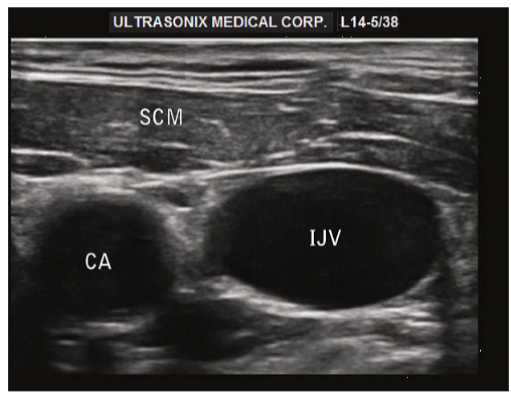

Ultrasound short axis view